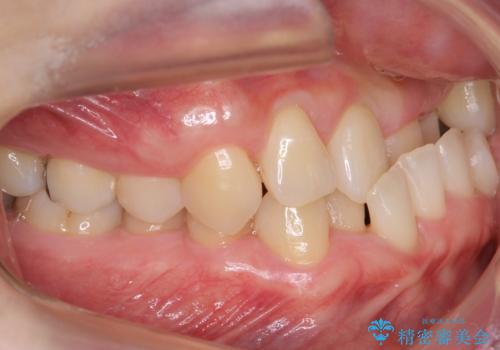

受け口 絶対に顎の手術はしたくない

- 受け口を主訴に来院。

下あごが大きく、顎の手術を含めた矯正をおすすめしましたが、手術は怖いので絶対にしたくないとのことでした。

歯並びのみを治す矯正は難しく、長期にわたる治療になるとご説明しました。

かみしめもあり、骨も固く、歯根も長いためなかなか歯が動かず、患者様も治療する側も忍耐を要する長期戦となりました。